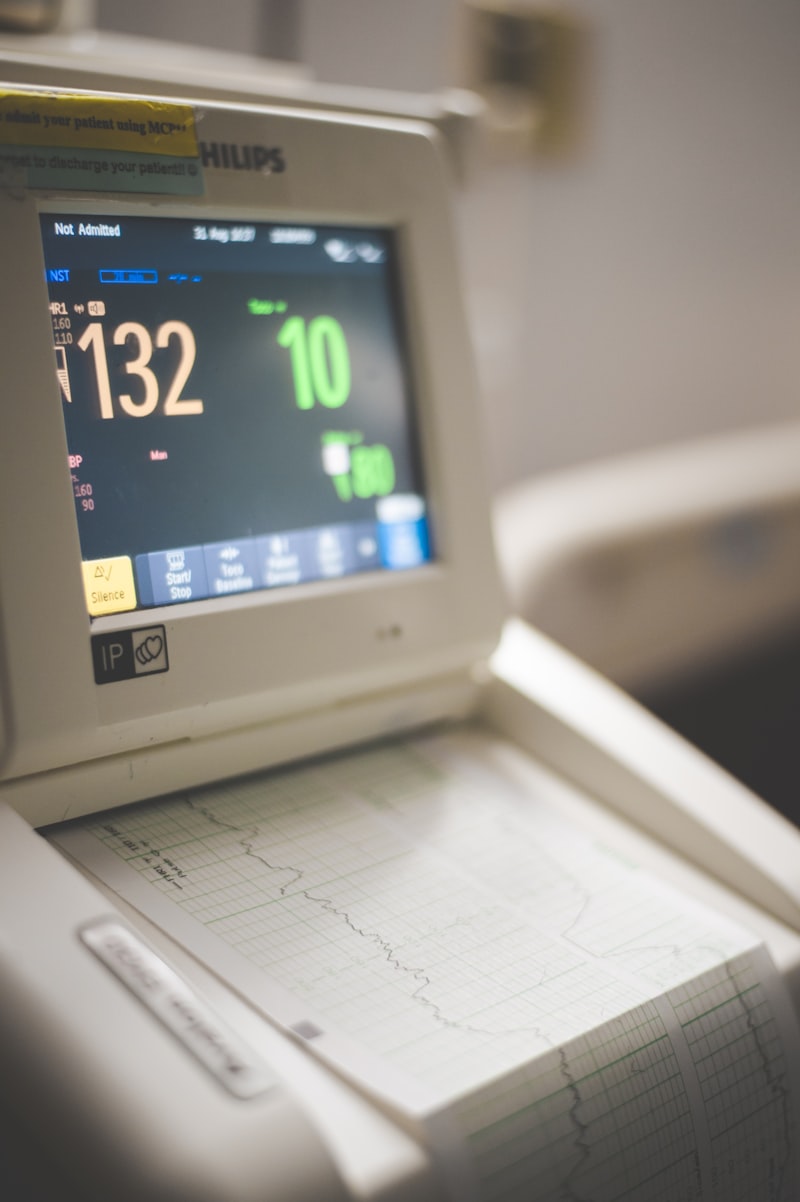

Prenatal Care

Dr. Soltani provides comprehensive prenatal care to support healthy pregnancies. Her OBGYN training ensures expert monitoring and guidance throughout your pregnancy journey.

- Pregnancy confirmation and dating

- Regular prenatal checkups

- Prenatal blood work and screening

- Nutrition and lifestyle guidance

- High-risk pregnancy monitoring

- Postpartum follow-up care